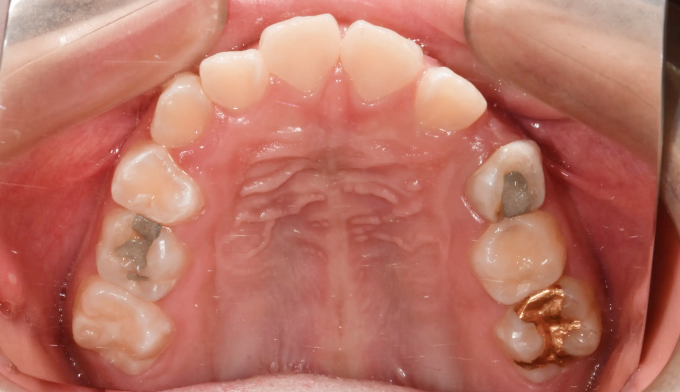

유치를 제때 뽑아주지 못하면 치아 맹출 순서가 뒤죽박죽이 되면 잇몸 안에서 맹출하지 못하게 됩니다.

본 케이스처럼 아예 치아의 각도가 누워버린 경우에는 억지로 교정장치를 부착하여 치아를 제 위치로 당겨주어야 합니다.

잇몸의 일부를 절개하여 교정장치 부착후 치아를 견인하였고 총 치료기간은 16개월입니다.